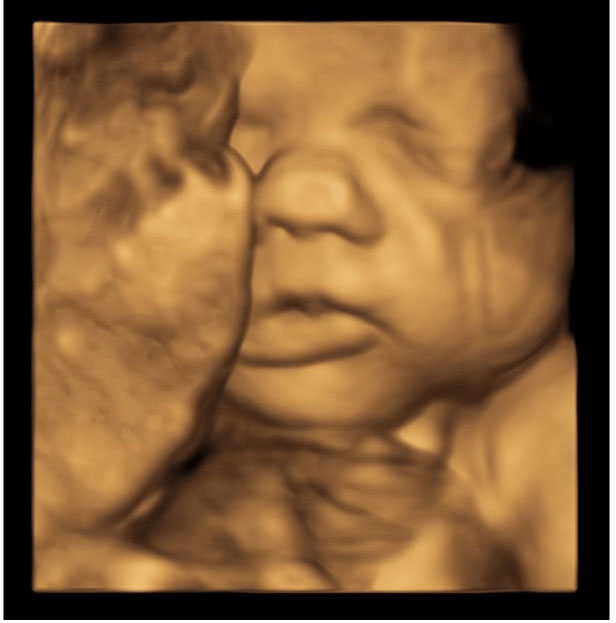

Mid Trimester Morphology Ultrasound

Most women will have a scan between 18-22 weeks to assess the fetal anatomy. At this time, the fetus is large enough to be seen clearly and so detailed assessment of many structures can be made, including the below:

- Face

- Brain

- Heart

- Arms and hands

- Legs and feet

- Spine

- Kidneys and bladder

It is not necessary to have a full bladder for this scan; however, some urine in the bladder may make it easier to see structures low in the pelvis.

The friendly staff at Western Imaging for Women will guide you through this ultrasound scan and point out the various features we are looking at. If possible, we try to obtain some 3D / 4D pictures of your baby’s face so you can start to see what your baby is going to look like!

Most of the time, the fetus looks completely healthy and we do not detect any problems. However, occasionally we do identify an abnormality in the fetal growth or development. At Western Imaging for Women, we have a range of Fetal Medicine specialists available to explain the ultrasound findings and what this means for your baby if we do find a fetal abnormality.

The third trimester is often a good time to obtain 3D or 4D pictures of the baby’s face and provided your baby is in a good position during the scan, we will always do our best to obtain these images for you.